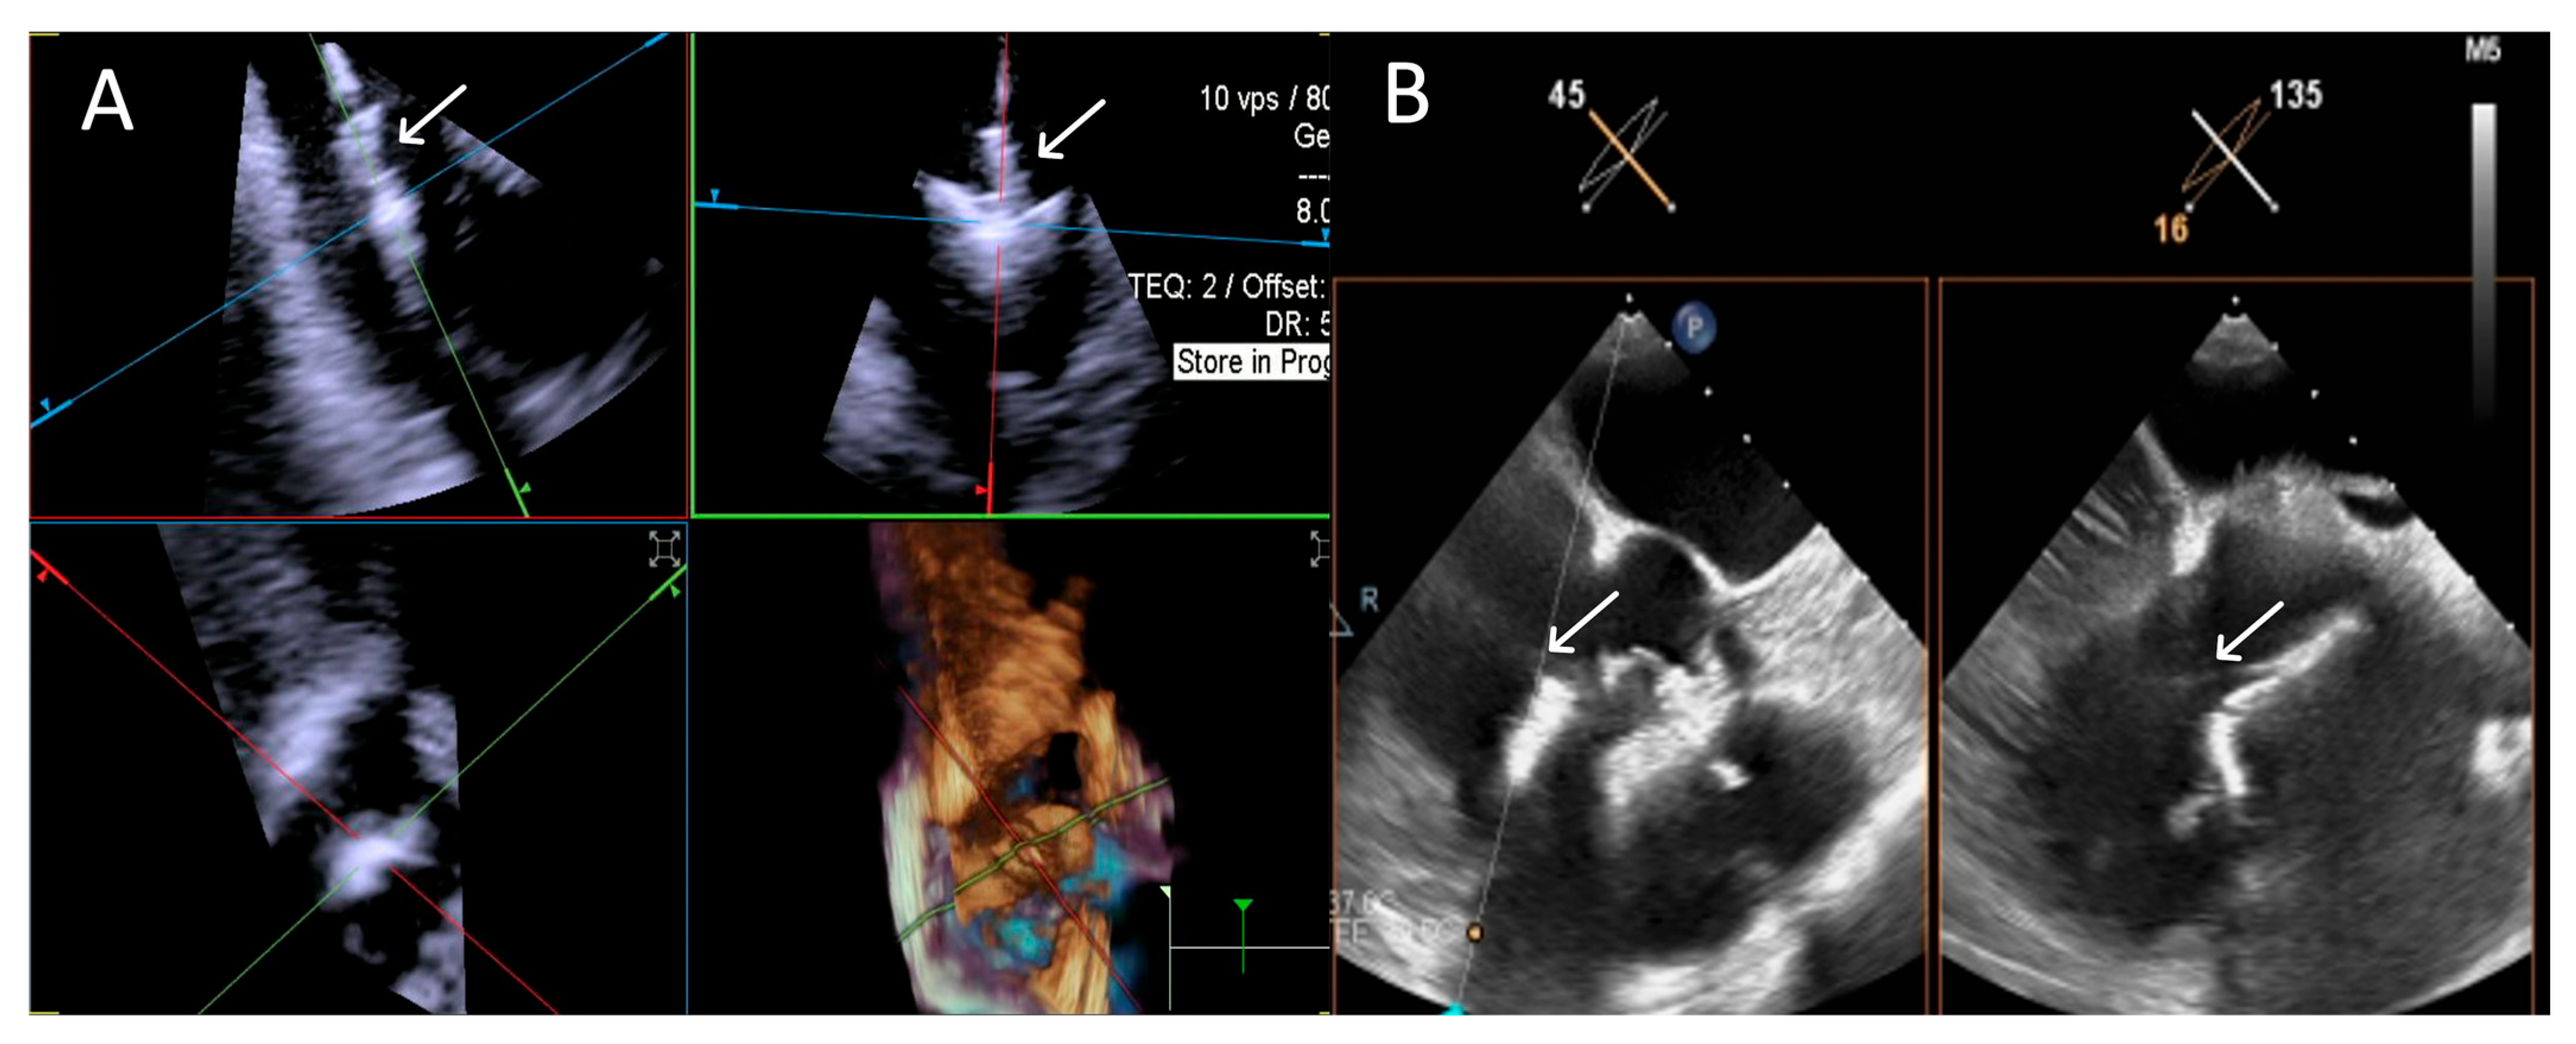

- Step number 4: ensuring perpendicularity and correct trajectory.

- Step number 5: clocking.

3.3.1. Step-by-Step Evaluation